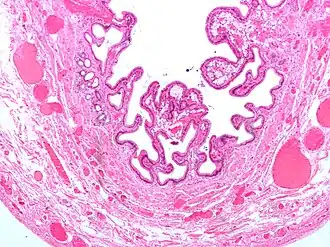

Микрофотография жёлчного пузыря при холецистите и холестерозе